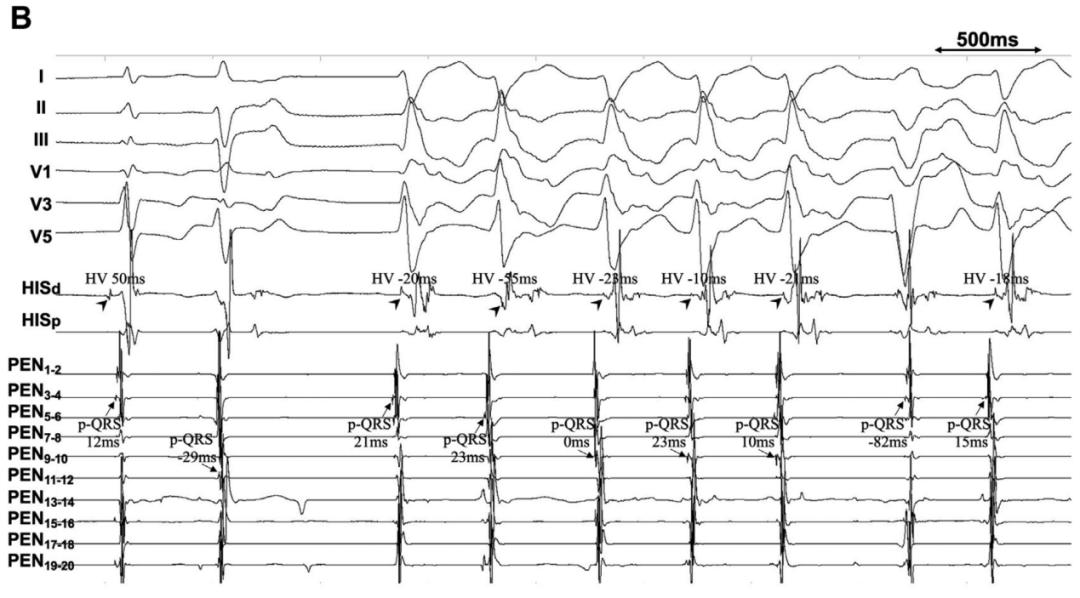

图4分别将四极导管置于希氏束区域、PentaRay高密度标测导管置于左前分支区域进行标测。

第1个搏动为交界性搏动(HV=50毫秒),顺向传导至左前分支(P最早/PEN3-4–QRS间期=12毫秒)。

第2个搏动表现出宽QRS波(124毫秒),电轴指向左上,呈右束支传导阻滞+左前分支传导阻滞形态。希氏束电位埋藏于QRS波中,P最早/PEN11-12–QRS间期=-29毫秒,所以这种异位搏动起源于左后分支的中部。

第3、4、5、6、7和9个搏动,均类似右束支传导阻滞+左后分支传导阻滞的形态(QRS波时限为141-170毫秒);HV间期均为负值,每次收缩前,左前分支区域的浦肯野电位均领先于希氏束电位,这表明在左前分支不同部位起源的异位电活动逆向激活希氏束。

第8个搏动,QRS波非常宽(188毫秒),电轴指向左上,呈左束支传导阻滞形态;看不到希氏束电位(埋藏在QRS之中或之后),P最早/PEN3-4-QRS间期为-82毫秒,这意味着该激动来源于右束支远端。